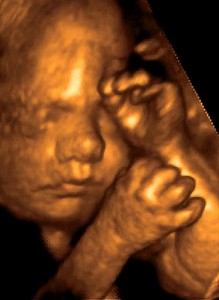

На 24 неделе беременности все системы и органы ребенка полностью сформированы. Лицо малыша уже стало почти таким, каким оно будет при рождении...